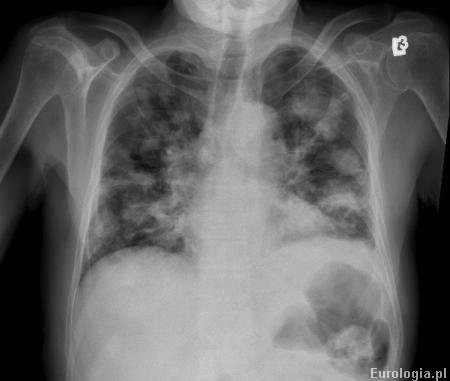

Fot. RTG klatki piersiowej - przerzuty do płuc w przebiegu zaawansowanego raka nerki.

Tak, najczęstszą lokalizacją przerzutów raka jasnokomórkowego nerki (łac. carcinoma clarocellulare) są płuca. Przerzuty raka nerki stwierdza się u blisko 30% pacjentów w chwili rozpoznania choroby. Najczęstsza lokalizacja przerzutów jasnokomórkowego raka nerki :

Płuca – 50-60%

Fakt powstania przerzutów dwa lata po operacji wymaga dalszej diagnostyki. Badania obrazowe pozwolą ocenić stopien zaawansowania choroby. Istnieje ryzyko, że przerzuty są innego pochodzenia niż rak nerki.